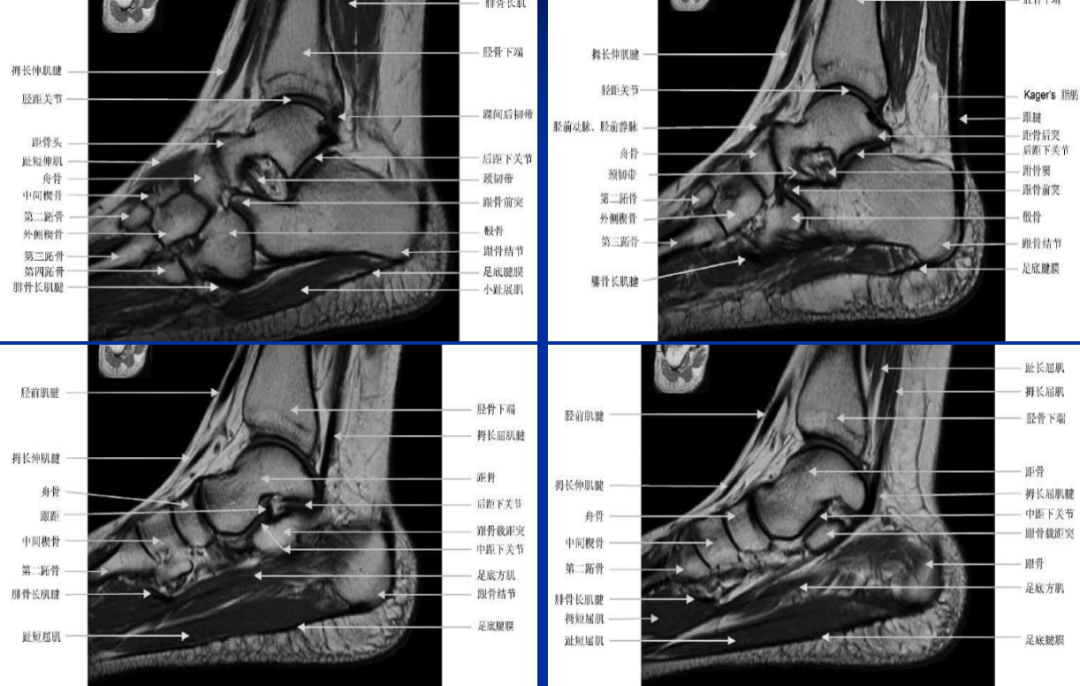

(二)跗骨窦解剖

跗骨窦是位于距骨颈和跟骨前上侧之间、由后内向前外走行的锥形空腔。其内侧为漏斗形的跗骨窦管,跗骨窦管的后方紧接载距突。跗骨窦是跟距后关节与前、中关节的分界,其中的主要结构包括脂肪垫、小血管、关节囊、神经末梢、滑囊和韧带(跟距骨间韧带、颈韧带、以及伸肌下支持带的内侧、中间和外侧根)。

依据管腔形态部位不同可分为两部分,前外侧部管腔较大为跗骨窦腔,后内侧部管腔较小且长为跗骨窦管。跗骨窦腔为漏斗形,上壁为距骨前下面,下壁为跟骨前上面,内侧壁为距骨头及距骨颈,外侧壁为距骨体,外口朝前外侧方向,内口朝后内方向。外口宽大,内口狭小为跗骨管。跗骨窦管位于跗骨窦腔后部 。

跟骨形态不规则,有六面和四个关节面,其上方有三个关节面,即前距、中距、后距关节面,分别与距骨的前跟、中跟、后跟关节面相关节组成前中、后、距下关节,中、后距下关节间有一向外侧开口较宽的沟,称跗骨窦,因其呈长管形,故又称为跗骨管。

跟骨距骨解剖

跗骨窦内有5条韧带(颈韧带、骨间韧带和伸肌下支持带的外、中、内侧束)、脂肪组织、动脉吻合支及神经末梢。

这些韧带稳定距下关节,并在关节囊前后构成了屏障。这些倾斜通过跗骨孔的韧带被称作是距下关节的“交叉韧带。”

距骨下韧带解剖

颈韧带位于跗骨窦腔外口稍后方,表面与深筋膜附着,封闭跗骨窦腔外口。它位于骨间韧带的中间,起于跟骨前内侧的颈结节止于距骨颈,是距下韧带中最强壮的韧带,此韧带联结距骨和跟骨,有限制距骨向前和向内移位、防止足过度内翻的作用。

骨间韧带较坚韧强厚,位于颈韧带后部,而且比颈韧带更靠内侧。在冠状面上该韧带与跗骨窦方向平均成45°角,其走行方向由后内斜向前外通过跗骨管。该韧带由前、后两束组成。距跟骨间韧带形如吊带,由于倾型走向和韧带纤维斜行穿过关节,在内翻和外翻运动过程中部分会被拉紧,有时被称作跗骨窦韧带。

骨间韧带由前、后两束组成。前束纤维起于跟骨沟的后部,跗骨管底壁前缘,附着于跟骨前距关节面和中距关节面后方,外侧与颈韧带相邻,向前上外行,止于距骨颈下方,附骨管顶壁。前束相对于后束更靠近前内方,侧面观可见其较后束更为倾斜。前束外形呈菱形或宽阔条索状。后束纤维附着于跟骨后距关节面前方,跗骨管后外侧部,走行向上内或后上内方,止于距骨后跟关节面前方,跗骨管顶壁即距骨沟的底部。

距跟骨间韧带后束纤维附着于跟骨后距关节面前方,跗骨管后外侧部,走行向上内或后上内方,止于距骨后跟关节面前方,跗骨管顶壁即距骨沟的底部。后束纤维位于关节运动轴下方,向前与伸肌下支持带的内侧根相邻。该韧带与关节囊前部紧密相贴,实为关节囊局部增厚形成.后束相对于前束更靠近后外方。侧面观见该韧带走行方向与足底平面接近垂直,部分稍偏向后。外形可呈梯形或宽阔的“V”字形。

距骨下韧带示意图

跗骨窦解剖

跗骨窦正常MRI表现

跗骨窦五根韧带

颈韧带:跟骨前外侧走向距骨颈部(1);跟距骨间韧带:最内后,从跟骨斜向距骨(3);下伸肌支持带内中外脚:位于跗骨窦外侧。